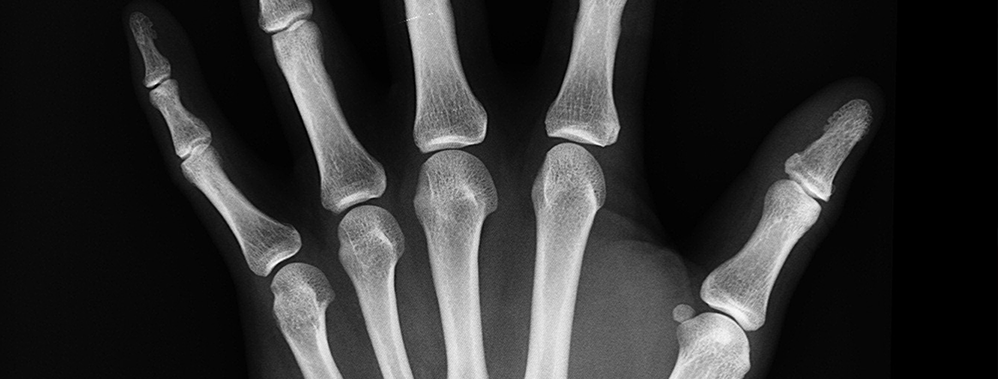

Les personnes atteintes d’arthrite chronique sont mal desservies par l’industrie médicale. En effet, les capacités actuelles de suivi et le piètre accès aux données signifient que les possibilités de traitement sont peu nombreuses. Parce qu’elle se manifeste habituellement dans les tissus mous des articulations, l’arthrite est difficile à déceler et à analyser efficacement avec les technologies d’imagerie médicale actuelles. Sans outils pour suivre avec précision et en temps opportun la maladie et son évolution, le médecin ne peut prescrire qu’un traitement général, mal adapté au patient.